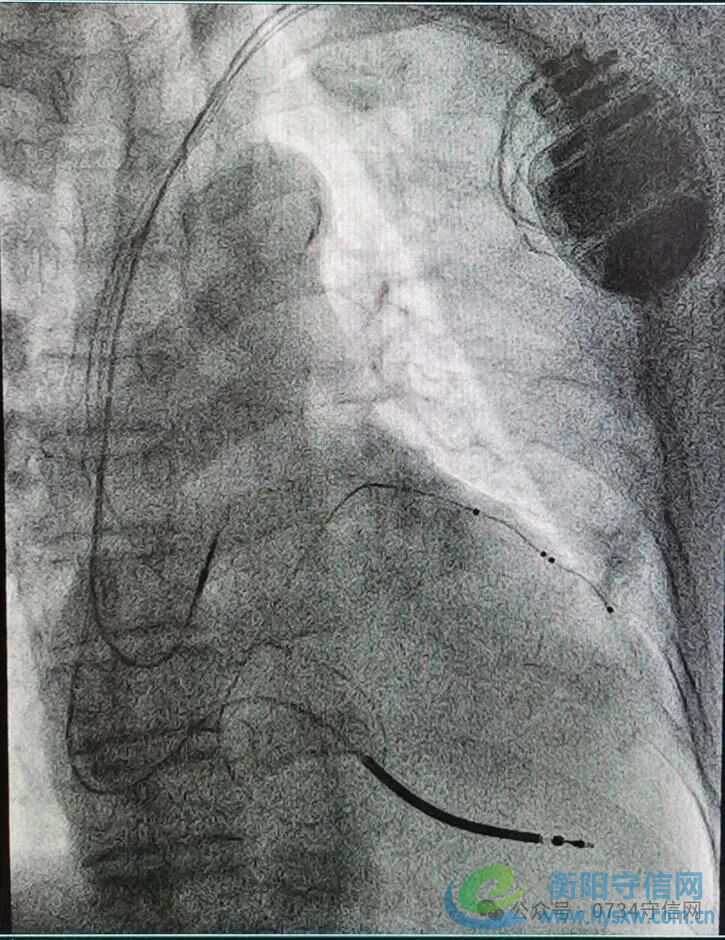

——衡阳市第一人民医院成功开展衡阳地区首例3.0T MRI兼容CRTD植入术

近日,衡阳市第一人民医院心血管内科专家团队成功为一名终末期心力衰竭患者,实施了衡阳地区首例3.0T磁共振(MRI)兼容心脏再同步化治疗心律转复除颤器(CRT-D)植入术。此项技术的开展,填补了区域内该领域的技术空白,标志着该院心脏起搏与电生理诊疗技术实现了跨越式提升,为当地心衰患者带来了新的生命守护方案。

作为心力衰竭治疗的“终极武器”之一,CRT-D(俗称“三腔除颤器”)是集治疗与防护于一体的高端医疗设备。它既具备心脏再同步治疗(CRT)的核心作用,又拥有植入式心律转复除颤器(ICD)的急救功能,为患者的生命安全拴上“双保险”。此次手术的关键突破在于“3.0T MRI兼容”。传统CRTD设备因受电磁兼容性限制,患者术后无法接受高磁场强MRI检查,而MRI作为多种疾病(如肿瘤、脑血管疾病)的重要诊查手段,其检查限制往往给患者后续诊疗带来极大困扰。3.0T MRI兼容型CRTD的成功应用,彻底打破了这一壁垒,患者术后可自由接受3.0T MRI检查,既不影响设备正常工作,又能获得全面精准的后续诊断,极大提升了治疗的安全性与便利性。